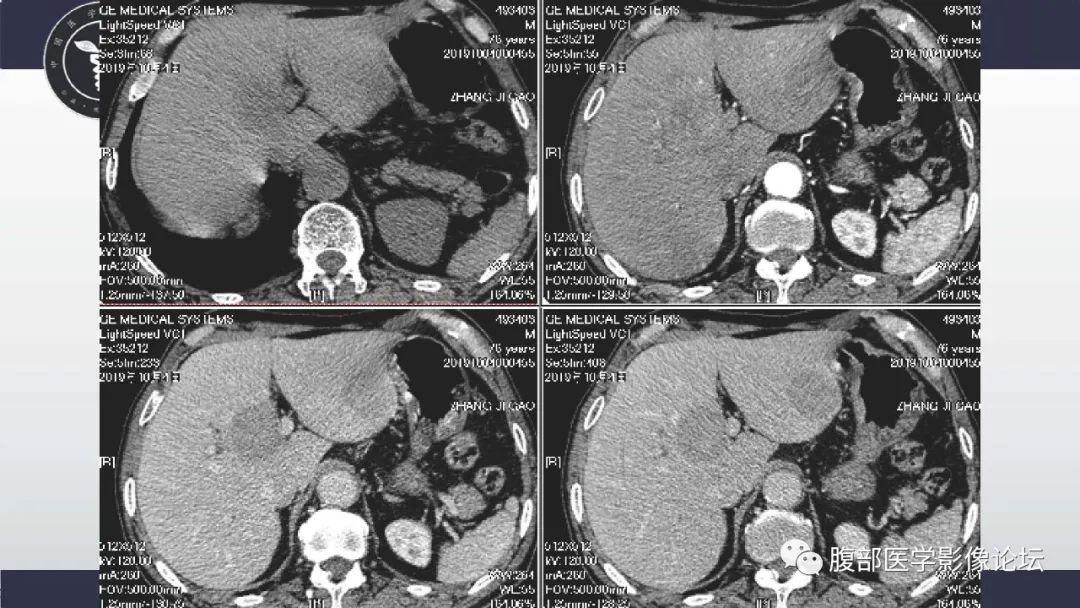

肝脏神经内分泌癌1例CT影像

李广明:病例1肝脏多发占位,部分病灶快进快出,部分渐进强化,延迟似乎可见包膜,左叶病灶可以一血管影 。疾病谱神经内分泌癌,淋巴瘤,胆管细胞癌,转移瘤。病灶延迟部分有环状强化 不太支持胆管细胞癌,强化方式也不符合一般转移瘤。有血管穿行需要考虑淋巴瘤,但动脉期这种强化方式不常见,神经内分泌影像表现符合。综合考虑神经内分泌癌>淋巴瘤,建议核磁检查。 医学百科网 | YxBaike.Com

向前相后:1.病灶多发,肝左叶病灶内可见血管影,强化中度,包膜不明显,老年人,先排除转移,在排除淋巴瘤,最后排除神经内分泌肿瘤。 医学百科网 | YxBaike.Com

陈应东:肝脏多发占位,边界不清,增强渐进强化,延迟期稍低于肝,内部血管穿行,密度较均匀,考虑淋巴瘤,鉴别nets,囊变坏死多见;icc不符合点无邻近包膜凹陷,无中央简质延迟强化。转移瘤:需要原发肿瘤病史。IMT:周围多有一过性灌注,容易囊变坏死,强化程度不一。 医学百科网 | YxBaike.Com

赵绍武:肝内多发肿块,部分血管穿行,强化不一,考虑神经内分泌肿瘤,鉴别淋巴瘤,转移瘤 医学百科网 | YxBaike.Com

:肝脏多发占位,部分病灶快进快出,部分渐进强化,延迟似乎可见包膜,左叶病灶可以一血管影 。疾病谱神经内分泌癌,淋巴瘤,胆管细胞癌,转移瘤。病灶延迟部分有环状强化 不太支持胆管细胞癌,强化方式也不符合一般转移瘤。有血管穿行需要考虑淋巴瘤,但动脉期这种强化方式不常见,神经内分泌影像表现符合。综合考虑神经内分泌癌>淋巴瘤,建议核磁检查。 医学百科网 | YxBaike.Com

Self:肝脏多发肿块,增强轻度强化,内见血管穿行,考虑淋巴瘤。

罗晓红:老年男性,肝右叶下段病灶为多发小囊样改变,猜个ICC。IMT、神经内分泌待排!! 医学百科网 | YxBaike.Com

影子:老年男性,肝内多发病灶,低至中度强化,动脉期有血管穿行征,静脉期与延迟期有晕征,优先考虑EHE,需要同转移瘤(缺乏靶征与其他部位原发恶性肿瘤病史,实验室检查无特殊,不太支持)与淋巴瘤(强化不均匀,脾脏不大,未见到淋巴结增大等不支持)。